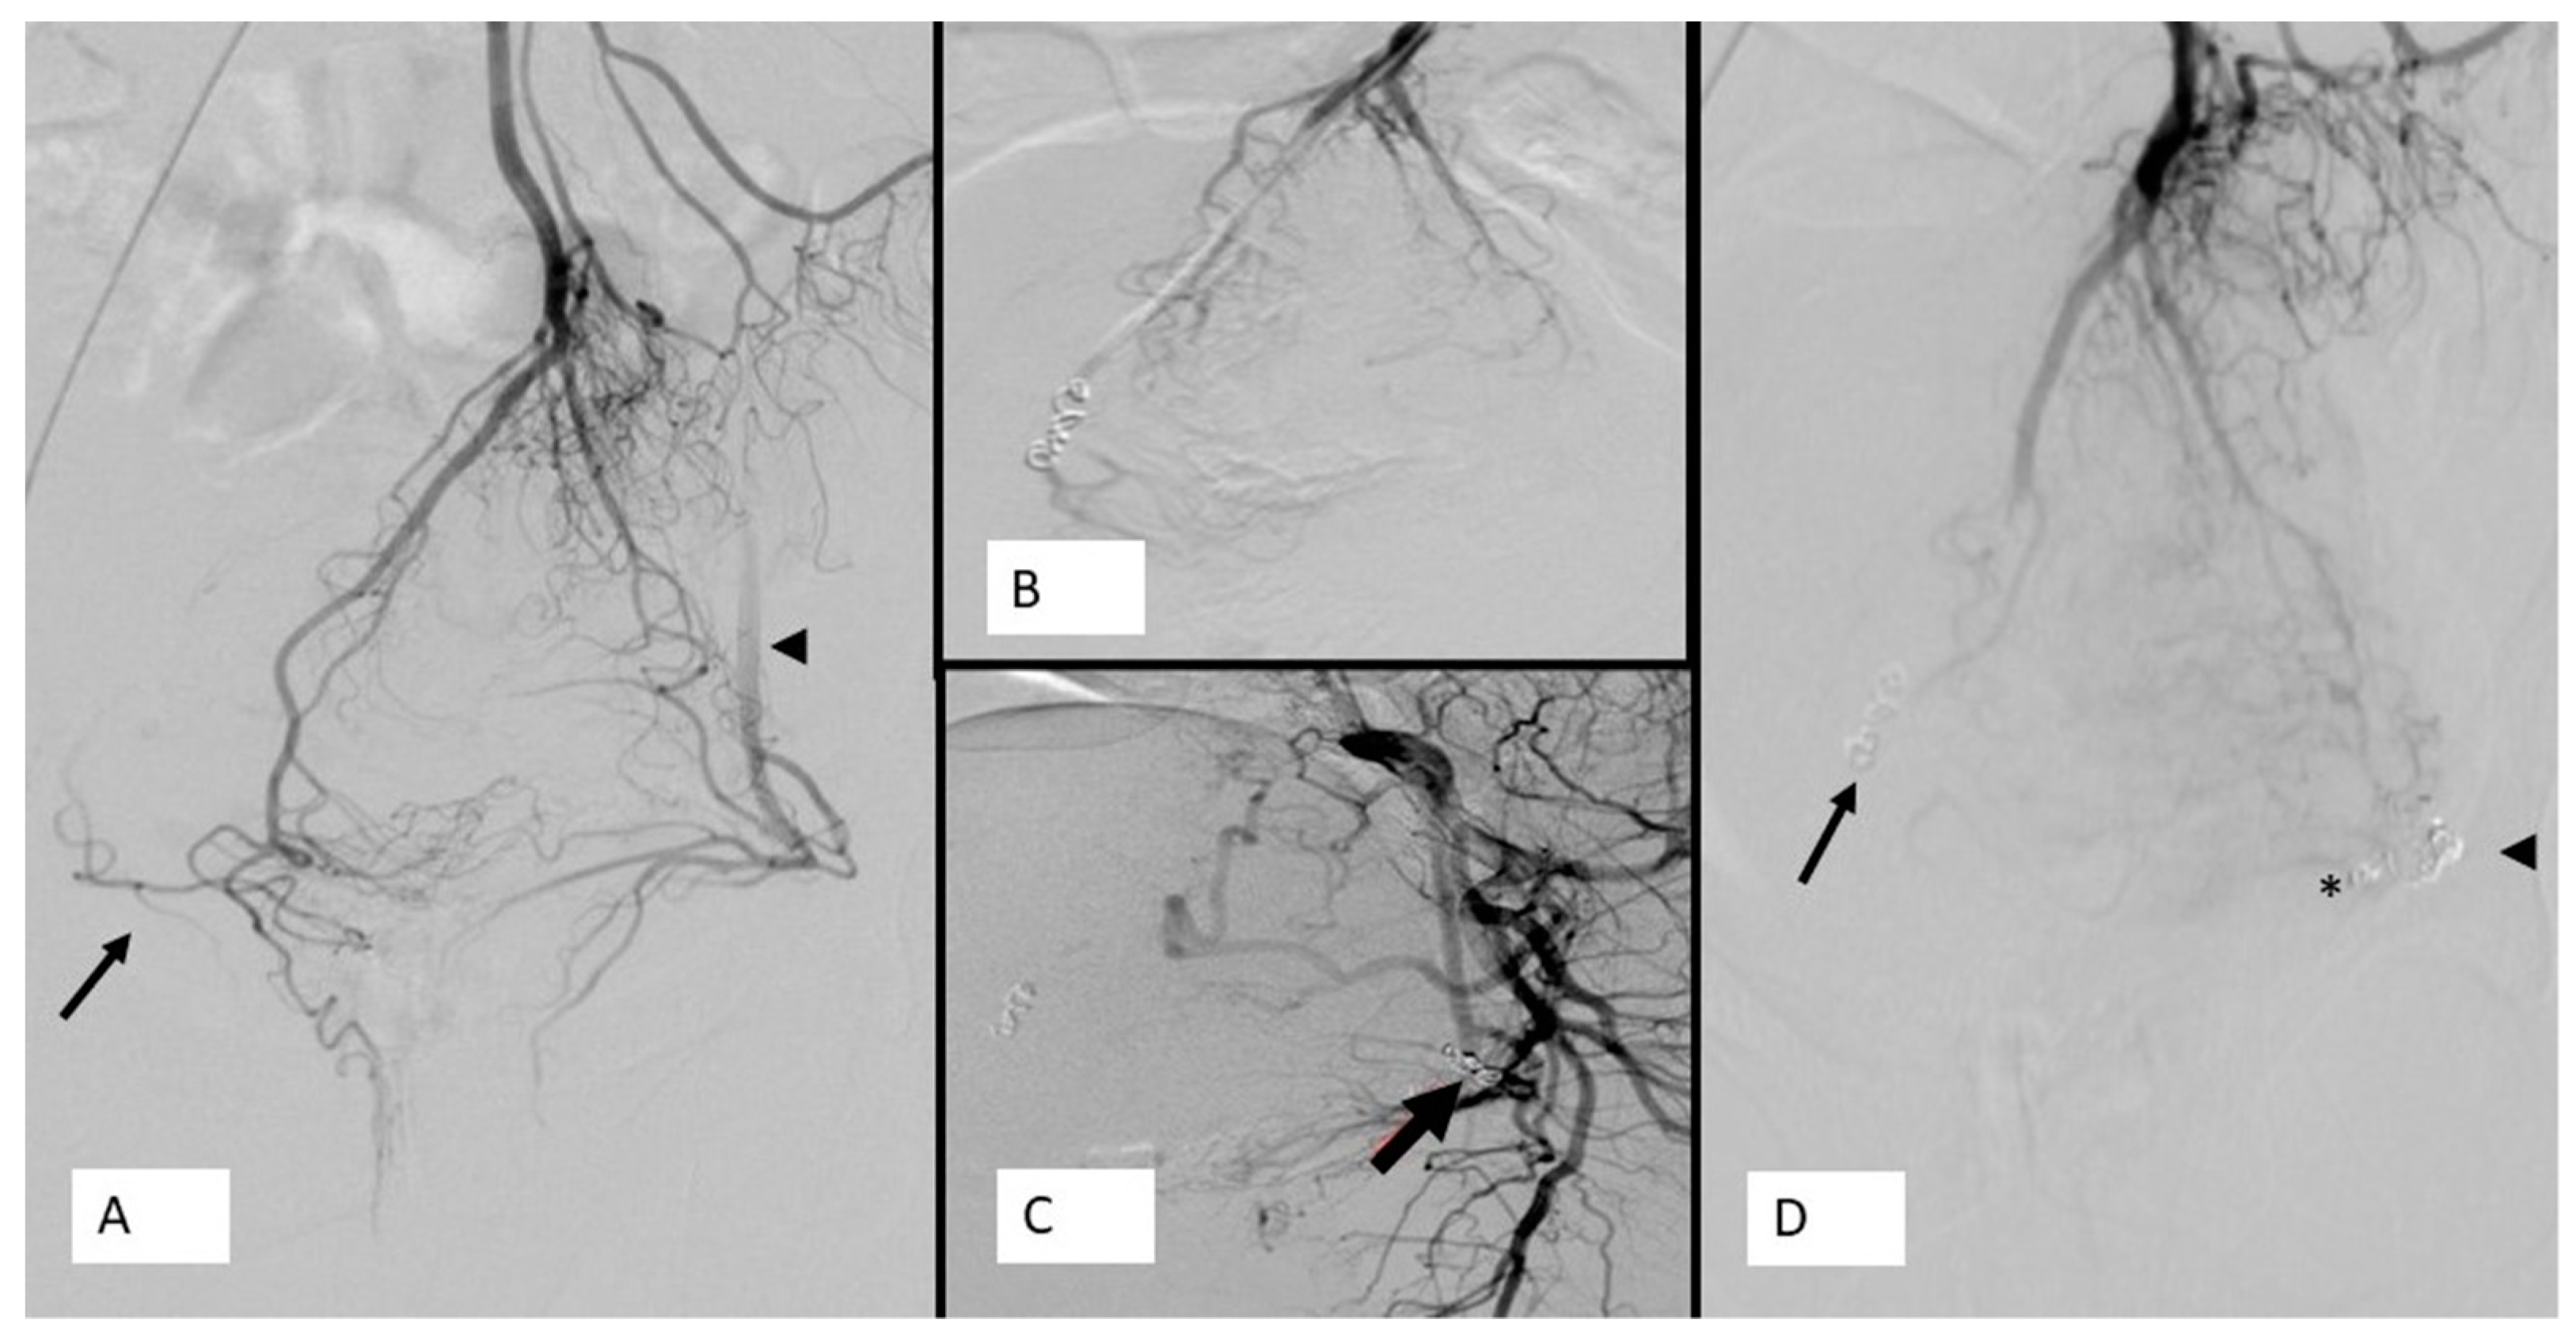

Rectal Artery Embolization for Hemorrhoidal Disease Anatomy

Rectal Artery Embolization for Hemorrhoidal Disease Anatomy Hemorrhoid Embolization Cpt Code Coding for the procedure is specific to the vascular group (arterial, venous) or purpose (tumor, organ ischemia, infarction, hemorrhage). Removal of a single tag/papilla is reported with 46220 excision. There is evidence of a arteriovenous fistula within the inferior pole left kidney which corresponds to the site of recent biopsy. The sra supplies the entire rectum, the mucous membrane of. Hemorrhoid Embolization Cpt Code.

Rectal Artery Embolization for Hemorrhoidal Disease Anatomy Hemorrhoid Embolization Cpt Code Some older versions have been archived. Removal of a single tag/papilla is reported with 46220 excision. An external thrombosed hemorrhoid may resolve into a skin tag or papilla, which the surgeon may remove. If there is more than one clinical indication requiring embolization, the code for the immediate indication for the embolization is the one that. The sra supplies the. Hemorrhoid Embolization Cpt Code.

Rectal Artery Embolization for Hemorrhoidal Disease Anatomy Hemorrhoid Embolization Cpt Code Removal of a single tag/papilla is reported with 46220 excision. There is evidence of a arteriovenous fistula within the inferior pole left kidney which corresponds to the site of recent biopsy. If there is more than one clinical indication requiring embolization, the code for the immediate indication for the embolization is the one that. Coding for the procedure is specific. Hemorrhoid Embolization Cpt Code.